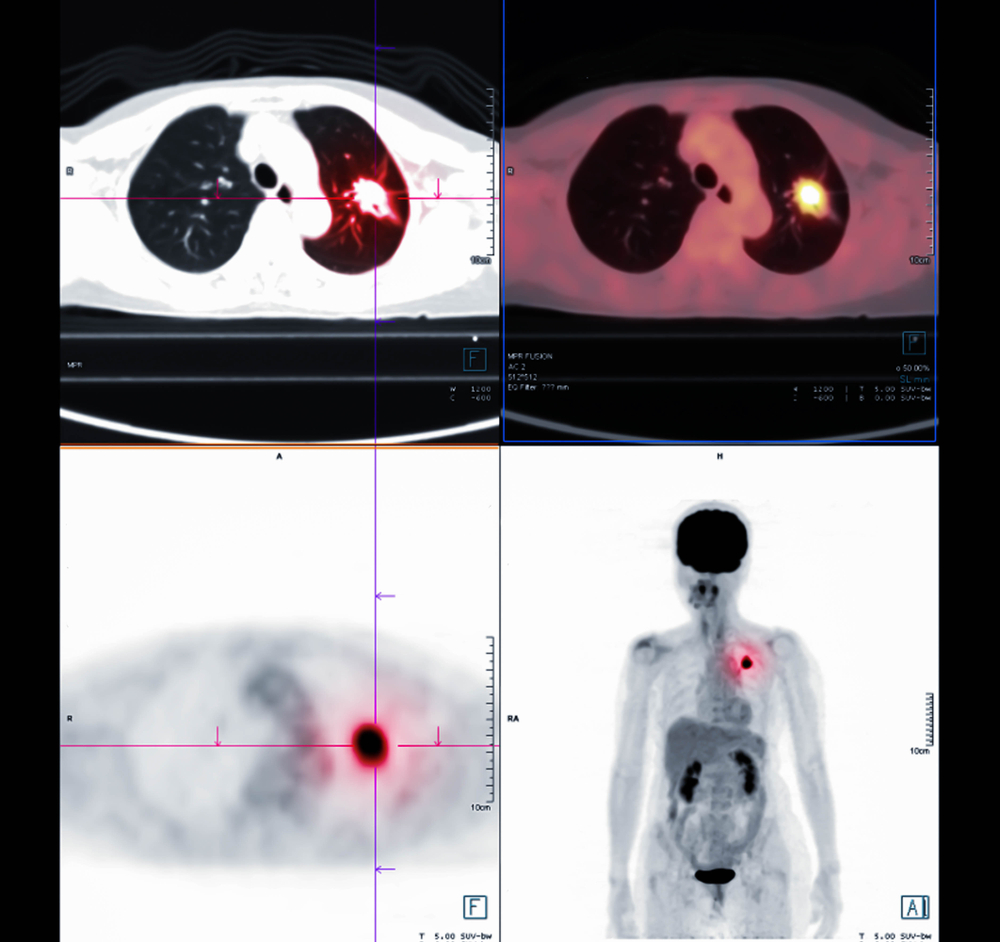

Dažniausiai PET tyrimas derinamas su kompiuterine tomografija (KT). Kompiuteris sujungia abu vaizdus ir suformuoja trimatį vaizdą, kuriame aiškiai išskiriamos sritys, kuriose ypač aktyvi medžiagų apykaita. Tokia vaizdų sintezė padeda tiksliau atskirti, ar plaučių srityje esančios masės yra gerybinės, ar piktybinės kilmės.

Toks tyrimas ypač vertinamas ieškant plaučių vėžio ar kitų ligų, nes leidžia pastebėti net ankstyvus pokyčius ir nustatyti vėžio išplitimo mastą.

Plaučių navikai ar kiti audiniai pasižymi didesne medžiagų apykaita, todėl jie sukaupia daugiau žymeklio ir tampa ryškiau matomi vaizdų analizėje. Tai leidžia gydytojui įvertinti, ar darinys plinta, kokia jo būklė, bei tiksliai nustatyti stadiją.

Gauti tyrimo vaizdai padeda gydytojams suplanuoti tinkamiausią tolimesnį gydymo planą ir parinkti veiksmingiausius gydymo būdus.